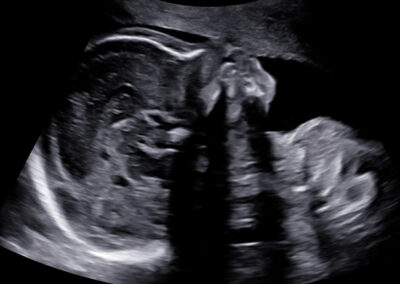

Genetický ultrazvuk Fetální echokardiografie Dopplerovské vyšetření krevního oběhu miminka a placenty Screening předčasného porodu Screening preeklampsie a zaostávání růstu miminka Vyšetření vícečetných těhotenství 3D-4D ultrazvuk Určení pohlaví miminka